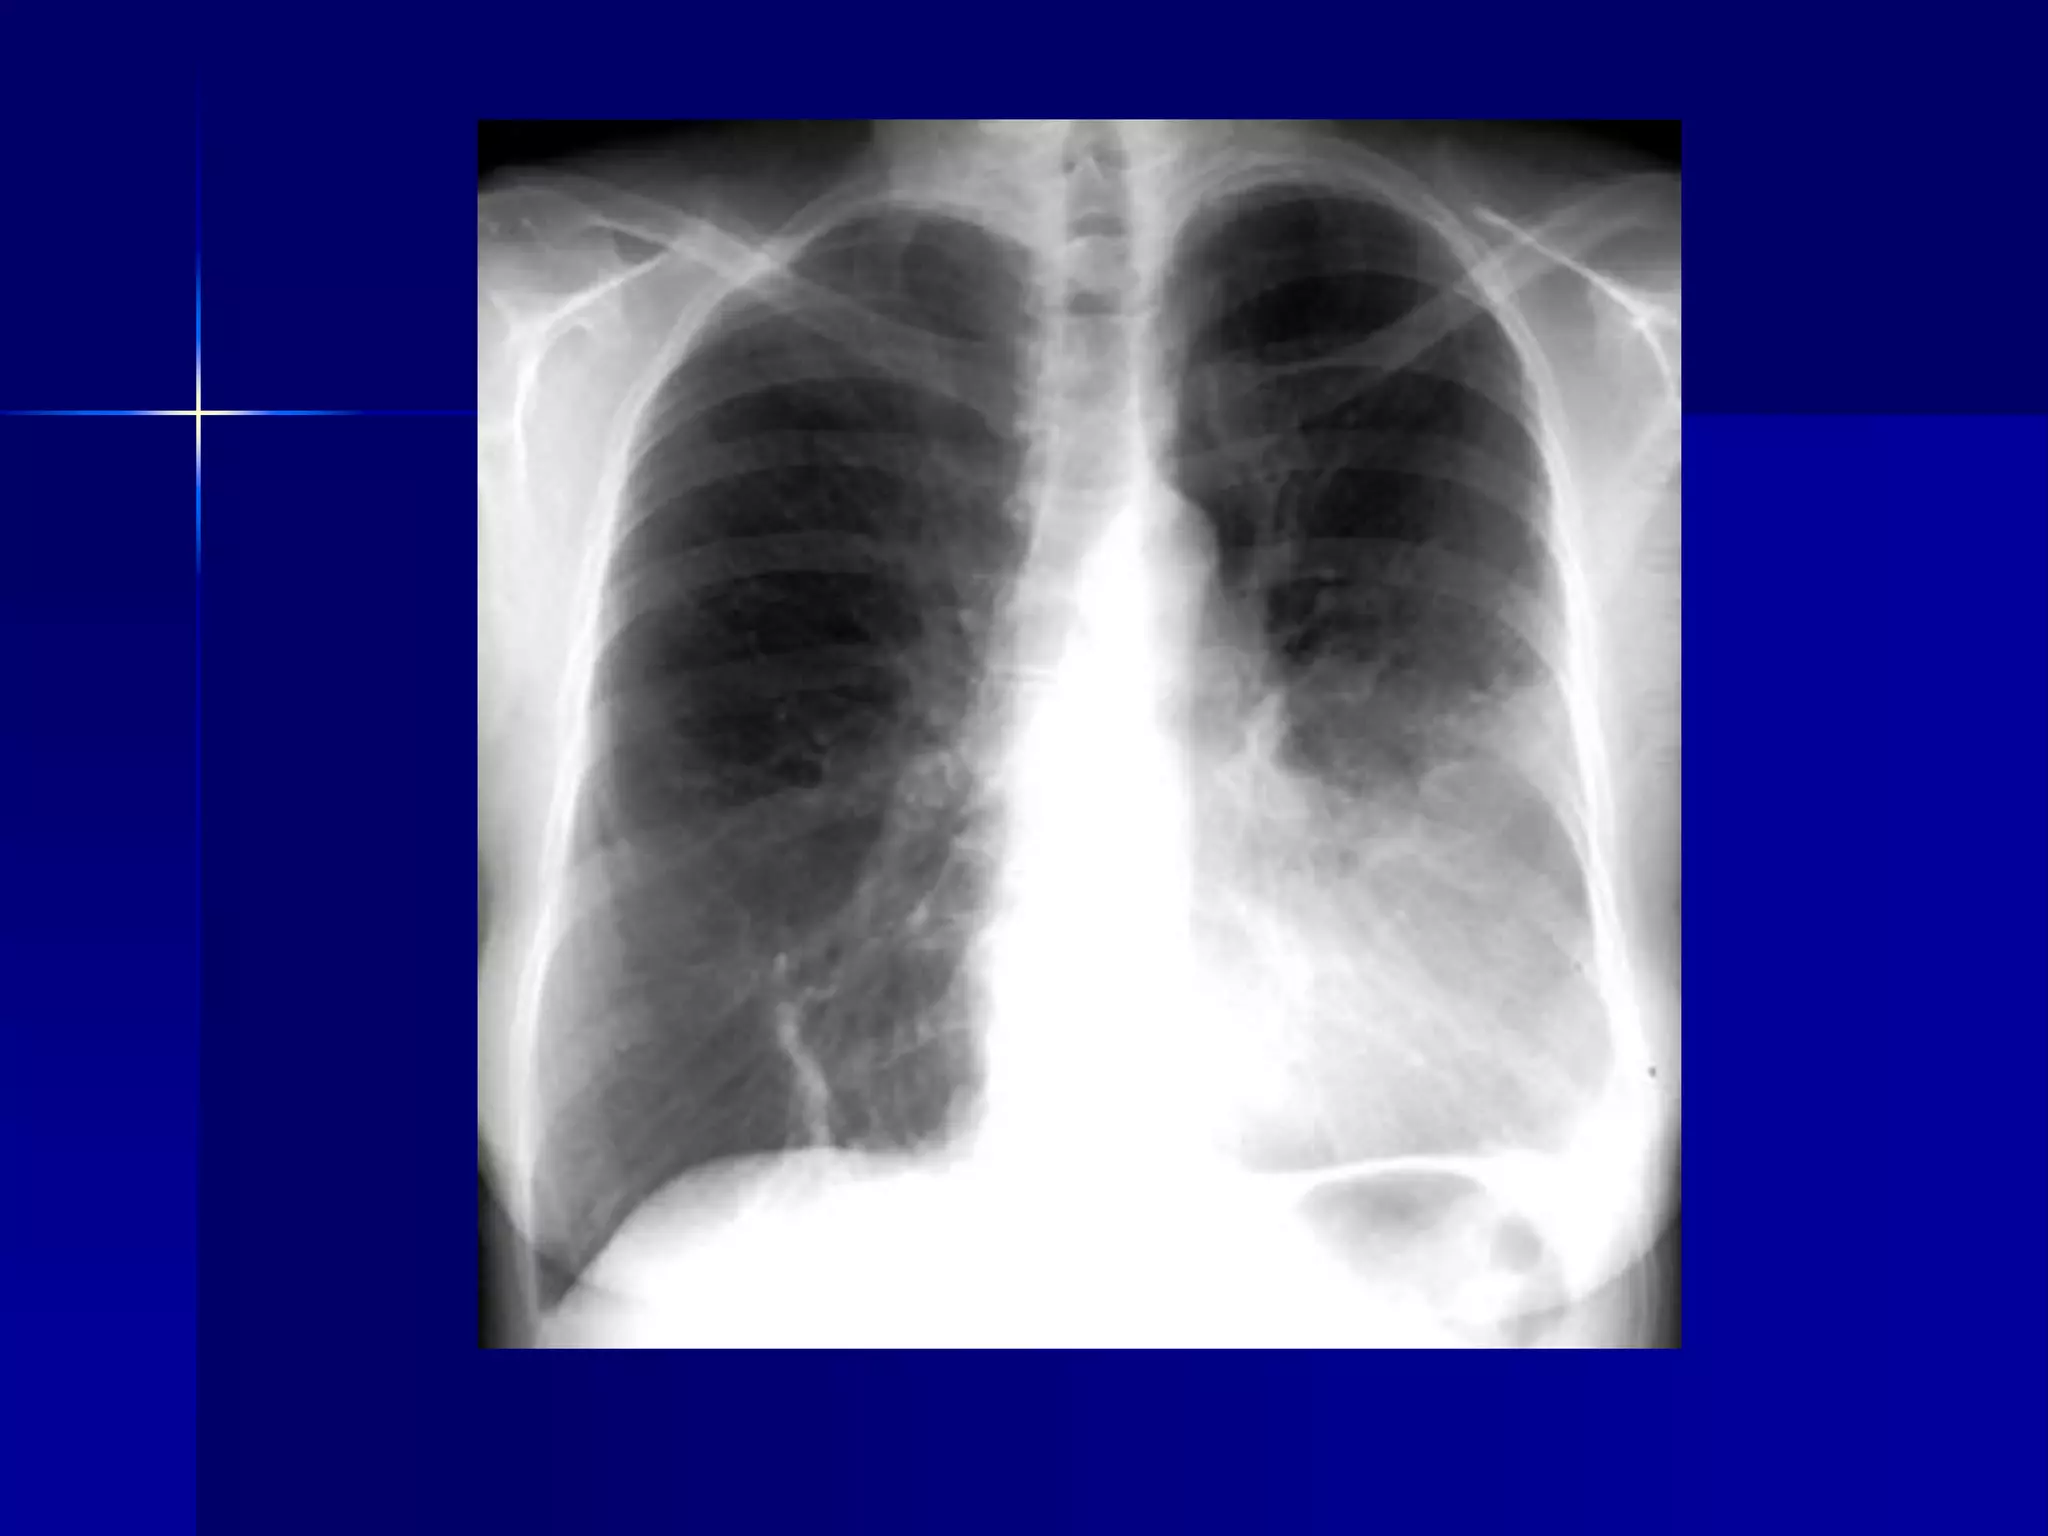

Atelectasis Left Lung

 Homogenous density left hemithorax

 Mediastinal shift to the left

 Diaphragmatic and heart silhouette

are not identifiable

Atelectasis Left Lung  Homogenous density left hemithorax  Mediastinal shift to the left  Diaphragmatic and heart silhouette are not identifiable